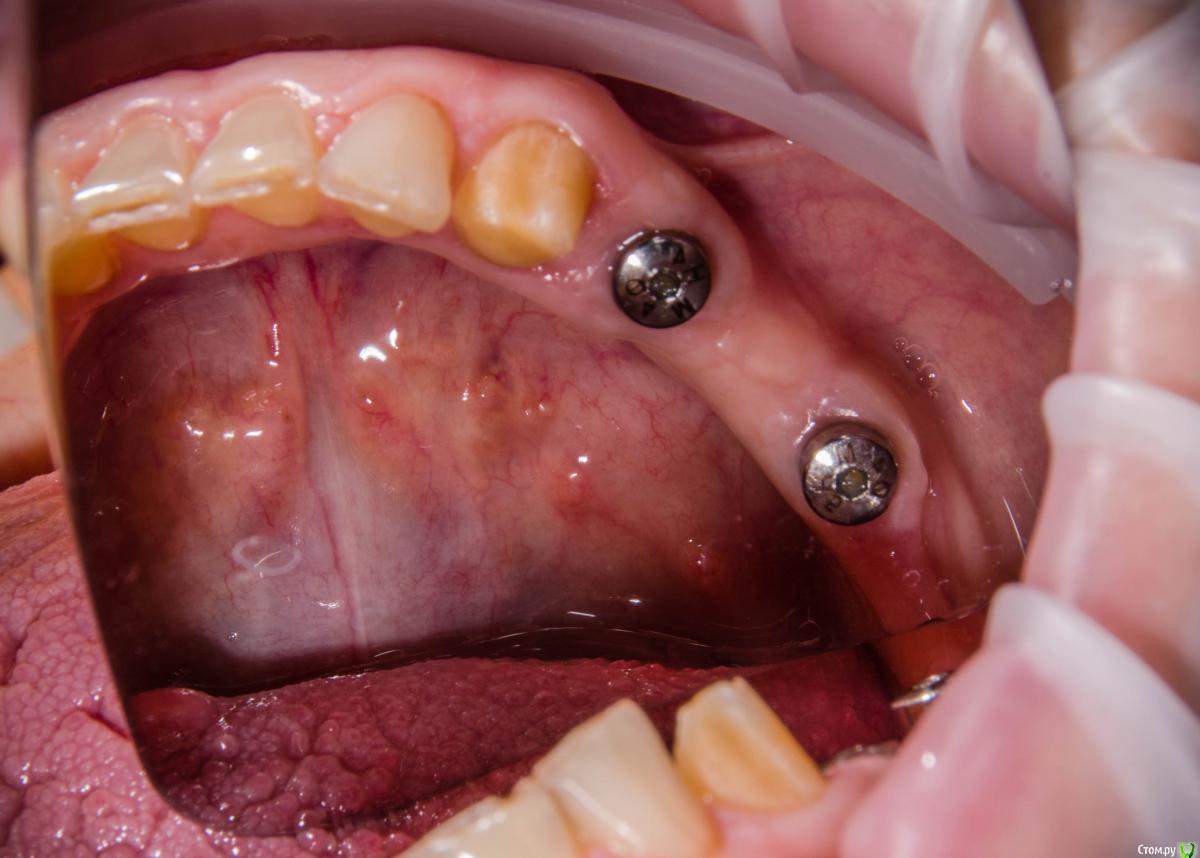

red_butler Опубликовано 7 февраля, 2017 Поделиться Опубликовано 7 февраля, 2017 когда до языка доберетесь? 1 Ссылка на комментарий

Astronaft Опубликовано 8 февраля, 2017 Поделиться Опубликовано 8 февраля, 2017 когда до языка доберетесь?Хороший вопрос. Как фибромы языка вырезать: по кругу ? И как потом заживает? Ссылка на комментарий

kamranchick Опубликовано 8 февраля, 2017 Автор Поделиться Опубликовано 8 февраля, 2017 когда до языка доберетесь?у нее 8 лет уже такая штучка, не растет и не мешает. а так, я думаю либо получать доступ как в Фрагискосе написано, либо коагулятором Ссылка на комментарий